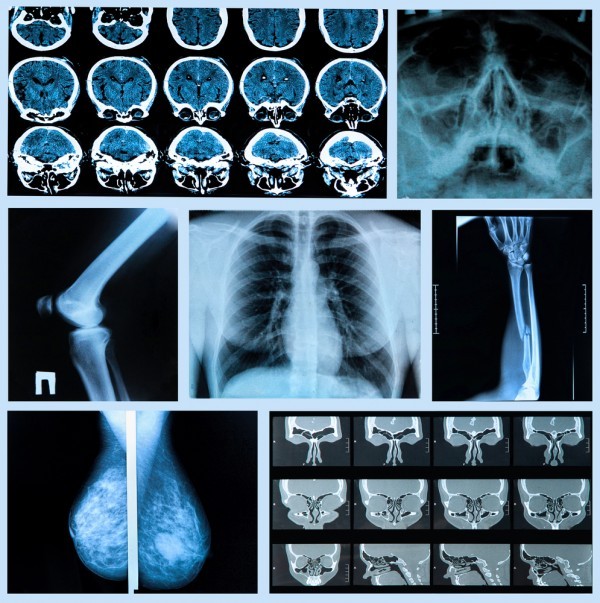

يجب علينا أن نحافظ دائما على صحة عظامنا حتى نتجنب ضعفها وإصابتها بالهشاشة والألم الذي يكون غير محتمل في معظم الأحيان، فالعظام هي التي تمكننا من الحركة والمشي والجدير بالذكر أن عدد العظام في الإنسان البالغ يبلغ 206 عظمة وهو يتكون من جزأين أساسيين هما اولا: الهيكل المحوري الذي يتكون من الجمجمة والعمود الفقري وعظمة القص والأضلاع وثانيا: الهيكل الطرفي الذي يتكون بدوره من الأطراف العلوية والسفلية وعظمة الترقوة وعظام الكتف والحوض، وعظام الإنسان تتكون من نوعين هما المكتنز والإسفنجي واتصال العظام بالعضلات الهيكلية والوتارو ترتبط ببعضها عن طريق المفاصل والأربطة وفيما يلي سوف نقوم بتقديم بعض النصائح الهامة لتتعرف كيف تحافظ على سلامة عظامك